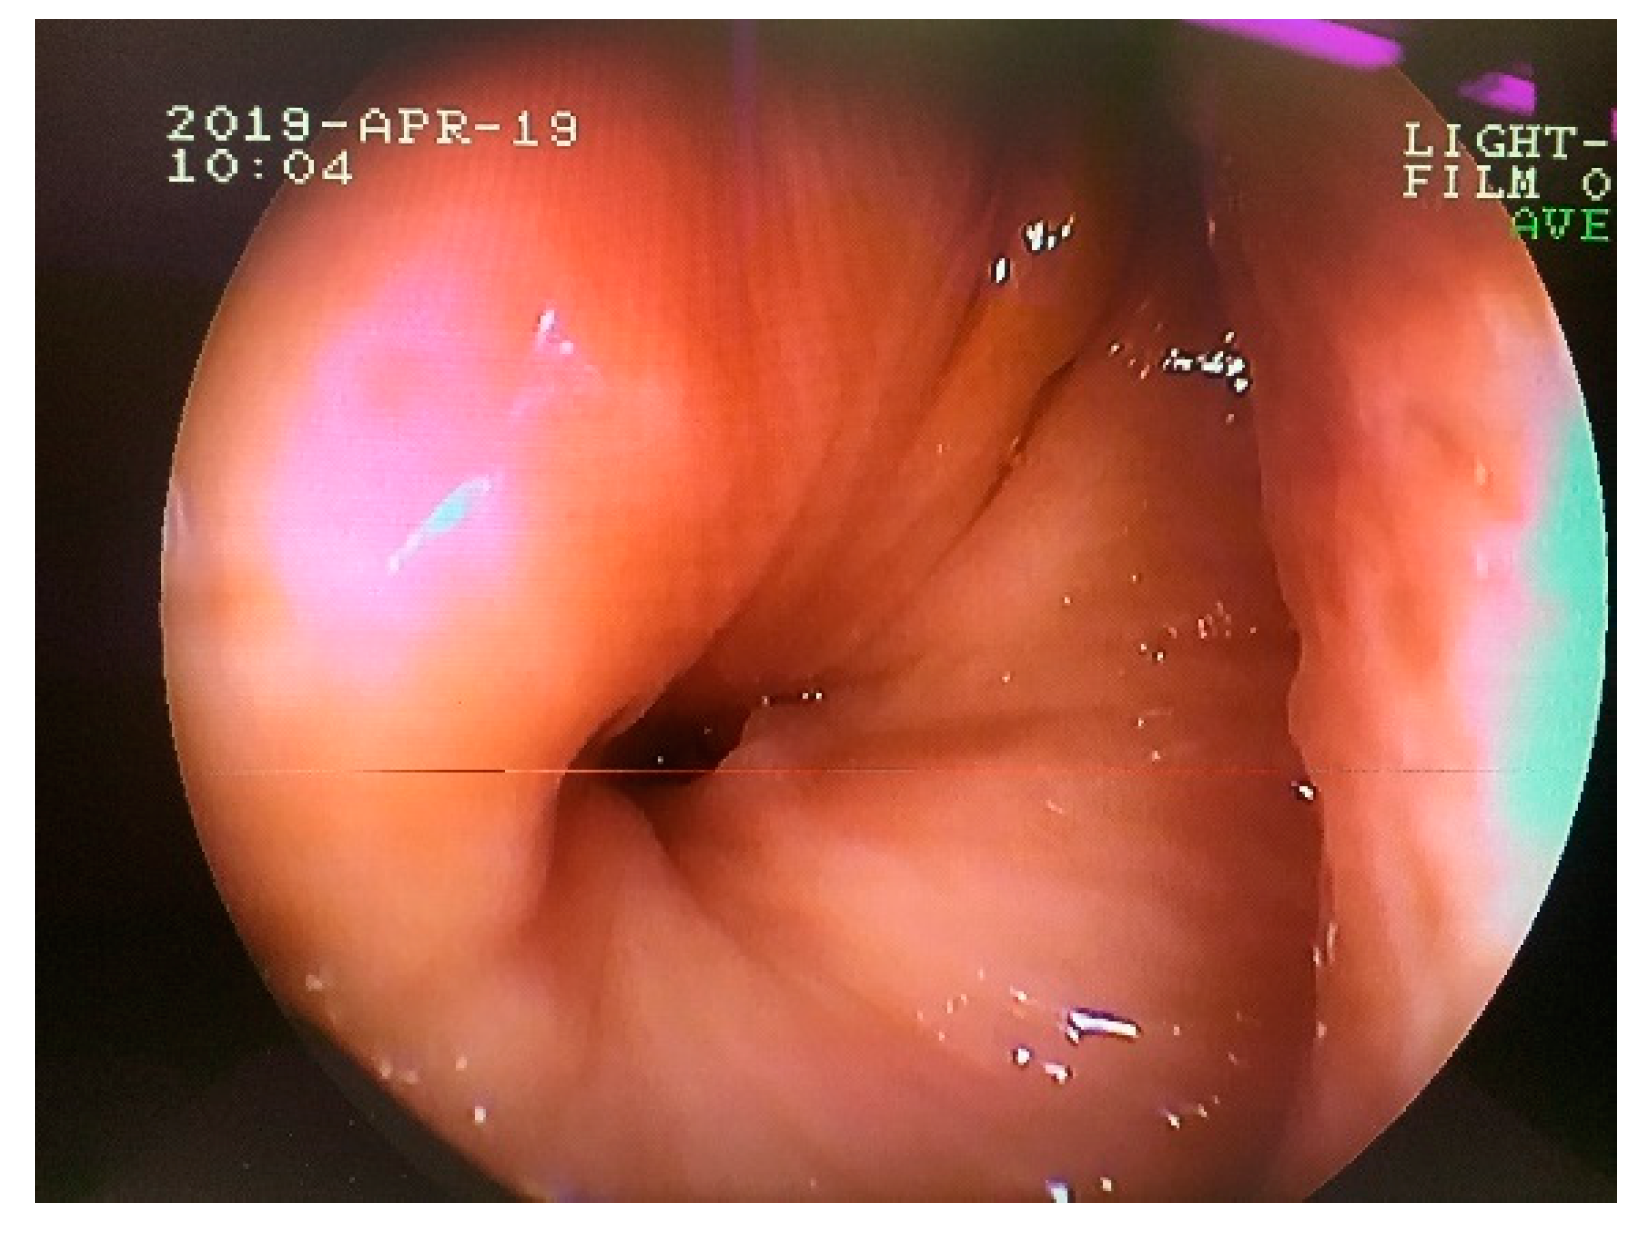

After surgery, the horse received an administration of procaine penicillin (80,000 IU/kg IM) and streptomycin (8 mg/kg IM), which was continued postoperatively for 10 days. During the first week, flunixin meglumine (1.1 mg/kg) was administered intravenously as anti-inflammatory therapy. After maxillary tooth extraction, the fistula was lavaged with physiological saline solution, debrided, and plugged with iodoform gauze immersed in plaster of Paris to allow granulation and to prevent the persistence of an oronasal communication. Three, four, and nine days later, under sedation (detomidine 0.02 mg/kg IV and butorphanol 0.01 mg/kg IV) the plug was replaced and the fistula was lavaged and debrided. Sixteen days after initial surgery, a polyvinyl siloxane plug (PVS) was placed in the alveolus. The PVS plug was changed once a week under sedation, as previously described. To improve the healing process, during each procedure fistula irritation with surgical gauze and a miniature tube brush was performed, and a new dental impression material plug was molded and inserted. Eight weeks later, endoscopic examination revealed that the oral opening of the fistula was filled with granulation tissue and mucosa, but the persistence of a 2 mm-diameter oronasal communication in the apical region of the alveolus was detected.

The apical part of the plug was remodeled and adjusted to the alveolus. The plug was frequently loosened, necessitating its replacement and resulting in the contamination of the nasal cavity with feed. In the 12th week of treatment, the plug was modified by adding a small plastic sleeve into the PVS packing material, to which a nylon thread was attached. Free ends were fastened to a button fixed on the surface of the maxillary bone (Figure 8). Additional injections of the fistula with platelet-rich plasma (PRP) were conducted in a once-weekly regimen for 3 weeks. Endoscopic examination performed in the 16th week of treatment revealed a markedly reduced tract of the fistula to a 1 mm diameter (Figure 9). Two months later, an autologous cancellous bone graft was taken from tuber coxae to promote bony fusion and revascularization. First, the oronasal fistula was filled with graft and the alveolar cavity was then covered with a modified polyvinyl siloxane plug, as previously described, for 4 weeks. Seven months after the initial extraction, endoscopic examination revealed the complete closure of the fistula.

Figure 9.

Transnasal endoscopic examination obtained 16 weeks after the initial surgery. Note the nasal opening of the persisted oronasal fistula at the level of 208 alveolus.